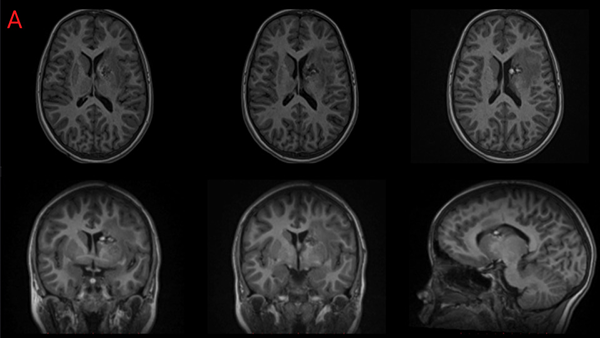

La paciente de 12 años presentó cefaleas, hemiparesia y pérdida de conciencia aguda que requirió soporte de Asistencia Respiratoria Mecánica durante tres días, dos meses previos a la cirugía. Debido al volcado ventricular se colocó un Drenaje Ventricular al exterior. Luego del episodio agudo la paciente se recuperó sin déficit motor. Mediante Resonancia Magnética por Imágenes (RMI) se diagnosticó un Cavernoma adyacente a la CI y sobre el Núcleo Caudado (NC) (Figura 1 A, B y C). El estudio de la RMI por Tensor de Difusión (Tractografía) expuso que la vía motora izquierda no estaba interrumpida completamente, quizá desplazada hacia lateral respecto de la rodilla de la CI (Figura 2).

Figura 2: Estudio de Tensor de difusión. Nótese la atenuación de la señal del haz motor en el hemisferio izquierdo.